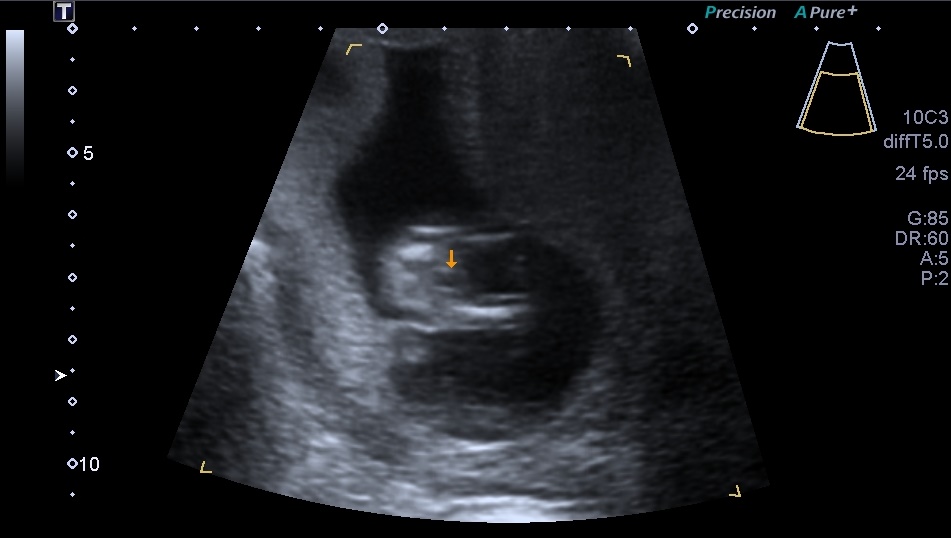

Attachment 20622Attachment 20621 Attachment 20623 Attachment 20624

I hope you can make a guess, i have to wait another 6-7 wks to find out the gender and i just like to hear your guesses

I'm gonna say boy too.the nub in your last pic is very boyish x